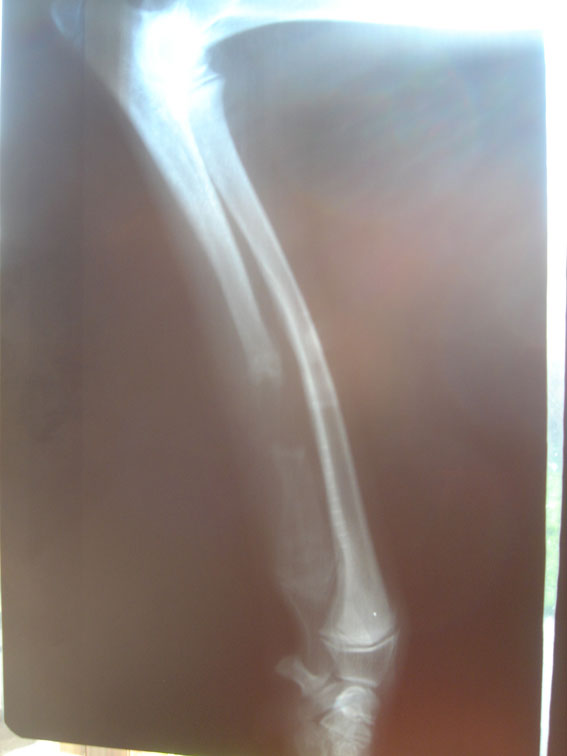

Na zdjęciach RTG po załamaniu lewej kości promieniowej obraz kości jest prawidłowy - tzn. są one prawidłowo zmineralizowane. Niemniej, są zdecydowanie bardziej narażone na urazy, których nie będzie można leczyć tak jak by to się działo bez osteotomii. Gdyby pies złamał kość promieniową i nie był w trakcie rehabilitacji po osteotomii, to szybko poradzilibyśmy sobie z tą sprawą. Podawalibyśmy preparaty przyśpieszające leczenie kości. W tym wypadku - NIE MOGLIŚMY. Oto zdjęcie RTG złamanej lewej kości promieniowej:

![]() powiększ klikając na zdjęcie ![]() powiększ klikając na zdjęcie Złamanie

Tarat po złamaniu został odwieziony karetką zwierzęcą do kliniki. Tam po 3 godzinach czekania w ciężkim bólu został poddany operacji. Kość została złożona za pomocą metalowej szyny i 5 śrub. Złamanie było o tyle niefortunne, że zlokalizowane było tuż nad punktem wzrostu kości promieniowej. Same nieszczęścia. Założenie implantu w takiej sytuacji niesie ryzyko kolejnych komplikacji - może doprowadzić do zakłóceń we wzroście kości promieniowej (implant jest tuż nad punktem wzrostu), naraża kość na infekcje co może mieć fatalne skutki dla gojącej się kości łokciowej. ![]() powiększ klikając na zdjęcie ![]() powiększ klikając na zdjęcie

Co do obrazu kości łokciowej to w trakcie tworzenia się nowej struktury

kostnej obraz na zdjęciach RTG jest bardzo mylący. Wielu lekarzy, w tym

i ten operujący na dyżurze Taratowi złamanie, ulega złudzeniu, że kości

te mają znamiona infekcji. W rzeczywistości tak nie jest. Kości

łokciowe odbudowując się tworzą nawet drastyczny obraz na zdjęciach

RTG. Ale jeżeli nie ma żadnych oznak infekcji: wysoka temperatura, ból, obrzęk,

powiększone węzły chłonne - to nie możemy ulec złudzeniu, że mamy do

czynienia z infekcją. Mimo wszystko, po założeniu implantu

wskazane było podawanie antybiotyku - osłonowo, żeby uchronić przed

ewentualną infekcją.